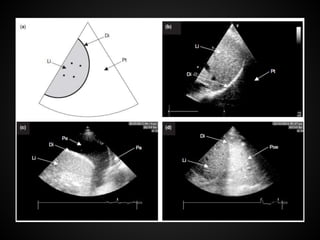

PLAX and PSAX

left lateral

decubitus position

LV LVOT

RV

LV

PLAX and PSAX leftlateral decubitus position LV LVOT RV RV LV